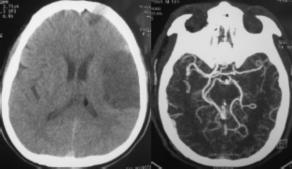

Hình 3.2b. Minh họa tắc động mạch cảnh trong hai bên - hai ca còn lại: TVG 74 tuổi (trái) và VHK 48 tuổi (giữa và phải), có tổn thương nhỏ vùng ranh giới, tắc động mạch cảnh trong hai bên với bàng hệ Willis từ hệ đốt sống thân nền qua động mạch thông sau.